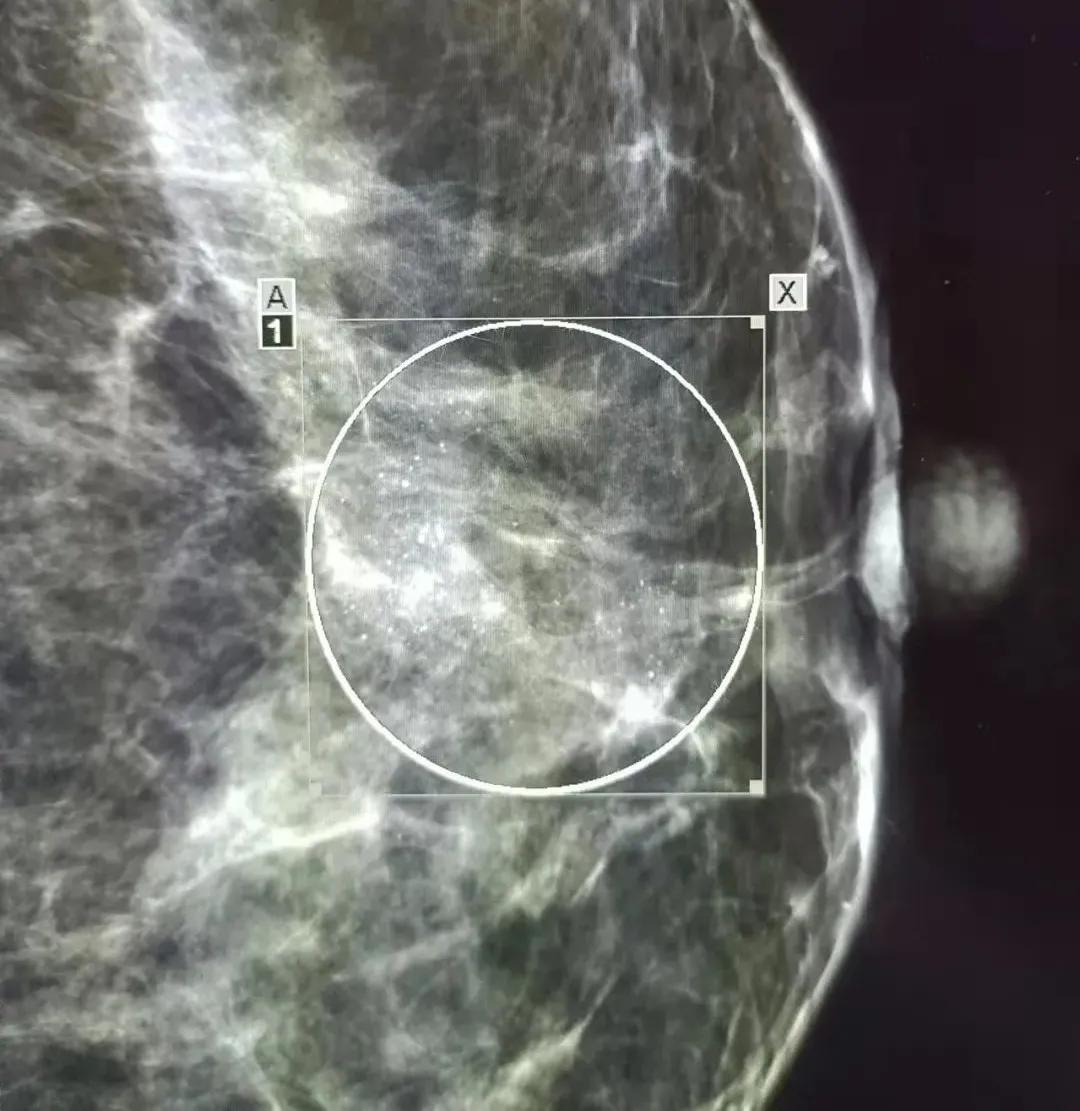

孙女士在1个月前体检时发现,左侧乳房上方有一片点状及模糊钙化,范围约4.9厘米×3.1厘米,在多家医院就诊后均不能排除乳腺癌的可能性,建议手术切除。这让爱美的孙女士无法接受。

圆圈里遍布小亮点,就是点状模糊钙化